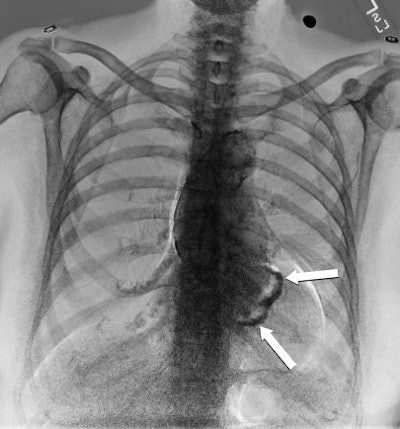

| Dual-energy bone image of figures above. The mitral annular calcifications are demonstrated (arrows). All images courtesy of Dr. Robert Gilkeson and medical student Sonali Mehandru, University Hospitals in Cleveland. |